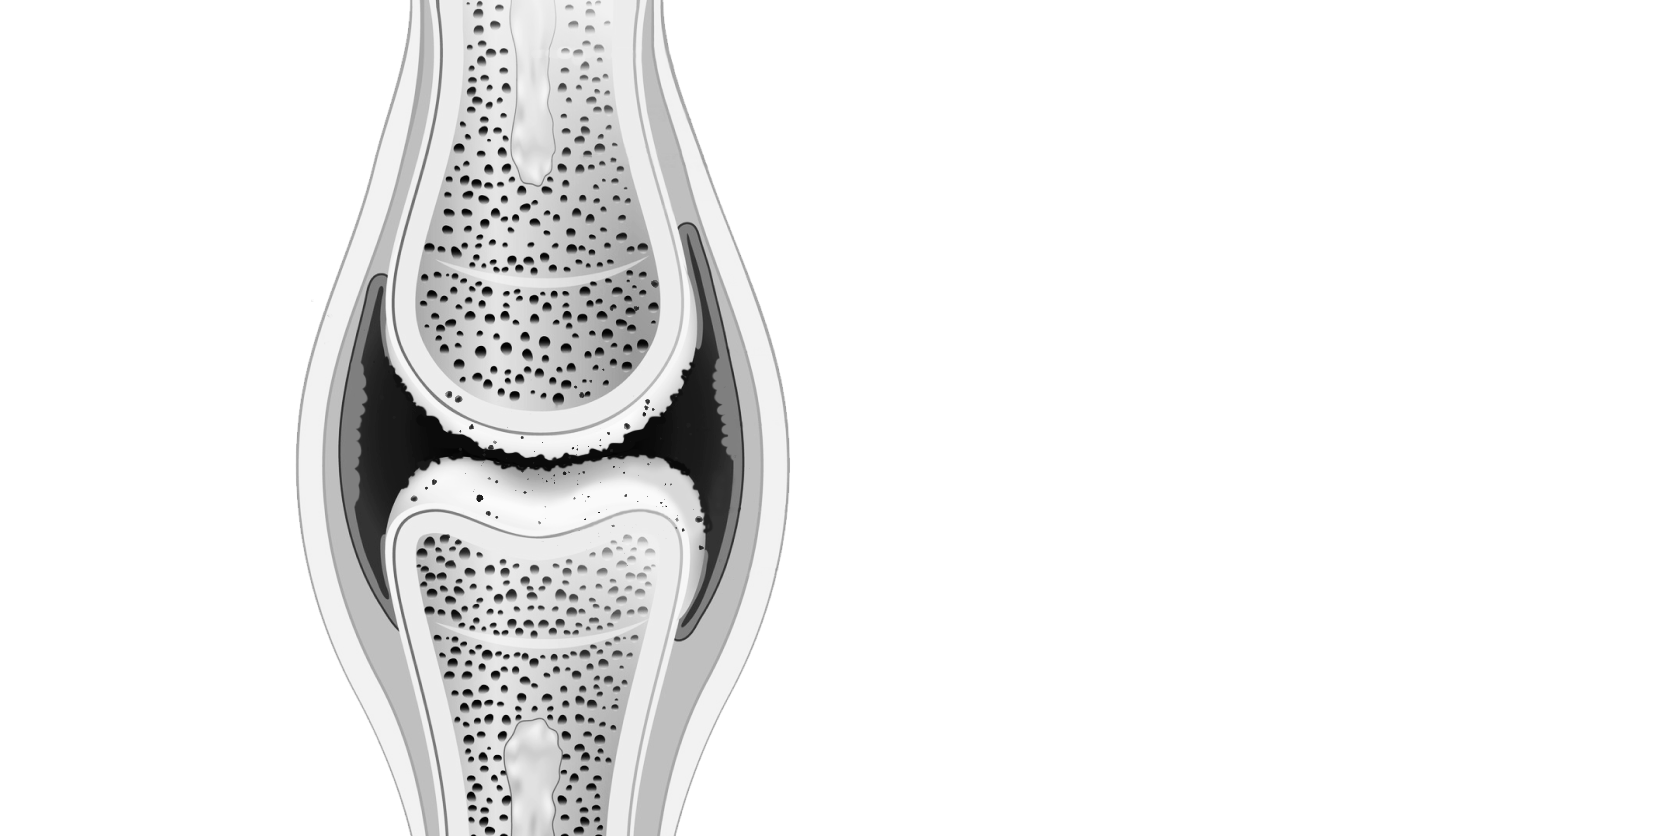

Хондроитина сульфат, гиалуроновая кислота, витамин Е, вспомогательные компоненты.